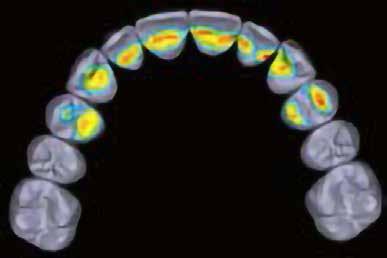

elkészített csavarozott, ideiglenes fogpótlást rögzítettünk a gyártó által előírt 15 Ncm-es nyomatékkal, az ideiglenes korona az okklúzióban és artikulációban nem vett részt (19., 20., 21. ábra). A front- és prémoláris régióban, amennyiben lehetséges, mindig nyílt gyógyulási protokollt választunk, azonnali ideiglenes restaurátumot készítve, így biztosítva elegendő időt a lágyrészek maturációjához (23, 24, 25, 26, 27). A kontrollvizsgálatok során havonta ellenőriztük az ideiglenes fogpótlás és az implantátum stabilitását, valamint a lágyrészek állapotát, korrekciós beavatkozás vagy az ideiglenes korona emergencia-profiljának változtatása nem volt szükséges (22. ábra). Két hónapos terhelésmentes időszakot követően, csont-tréninget alkalmaztunk részleges terheléssel, a teljes terhelést a hatodik hónap végére értük el, és megkezdtük a definitív protetikai ellátást. Az ideiglenes restaurátum eltávolításakor az alveoláris struktúrák tökéletes gyógyulását észleltük, a páciens ínye békés, reakciómentes volt, megfelelő mennyiségű keratinizált, feszes ínnyel rendelkezett (23. ábra). Az implantátum stabilitása Periotest-tel -8 értékű volt. Cerec Omnicam rendszerrel digitális lenyomatot vettünk (24. ábra), és a fogtechnikus (Prodont Silver Kft., Panyi János) által ragasztott, csavarozott hibridkerámia koronát készíttettünk nem indexált Ankylos C/ titanium-base fej felhasználásával, amelyet az előírás szerinti 15 Ncm-es nyomatékkal rögzítettünk (25., 26 ábra), majd ellenőriztük az okklúziót és az artikulációt (27. ábra). A beavatkozást követően 6 hónappal az alveoláris struktúrák stabilak, a röntgenfelvételen a csontállomány megtartott, a beteg panaszmentes, rágó funkciója kifogás-